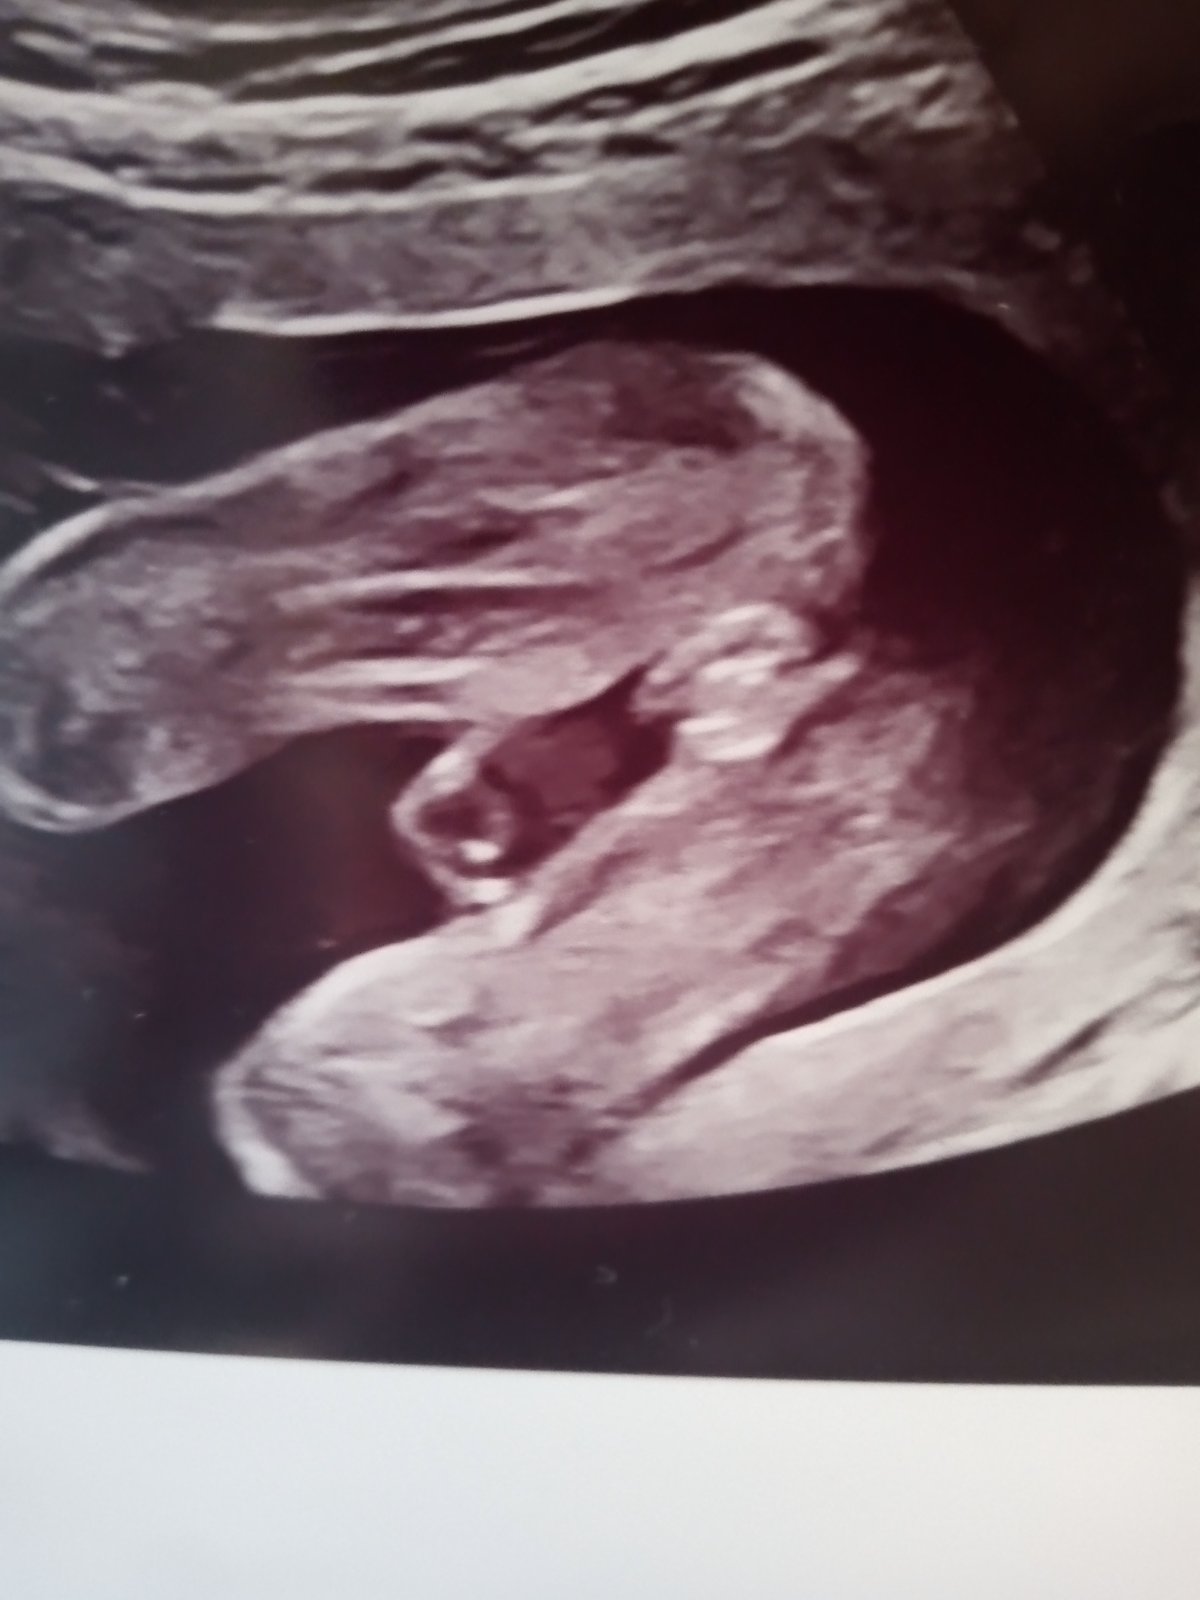

Pohlaví miminka ve 21. týdnu: Poradíte s tipem?

Ahoj, chtěla jsem se zeptat, mám za sebou druhý screening ve 21tt a konečně se nám odhalilo pohlaví (nebudu prozrazovat co mi řekl doktor, abych neovlivnila) ale byla bych ráda, kdyby jste omrkly fotku z utz (je to zespodu pohled mezi nožky) a tiply si, co vidíte. Nám se doteď mimco nechtělo ukázat a pořád se mi výsledku nechce věřit a bojím se něco nakoupit, třeba tu bude někdo znalejsi a uklidní mě :D díky

Holčička 🙂 A super fotka, mě řekli pohlaví taky jenom na screeningu, bez fotky..tak snad tomu můžu taky věřit 😁

Tak vám děkuji za uklidnění 🙂 Dr nám taky řekl holku, ale pořád sem tomu nemohla uvěřit :D vůbec netuším jak taková holka na utz má vypadat :D

holčička?